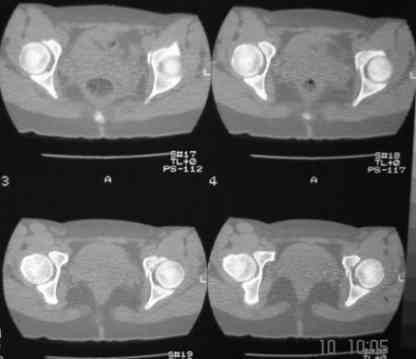

В больнице вправили вывих бедра, три недели на вытяжении. Беспокоят боли в левом тазобедренном суставе и левом крестцово-подвздошном сочленении. Ходит с тростью. Снимок - в приложении. Направил на КТ, заключение: разрыв симфиза и левого крестцово-подвздошного сочленения, переломы крыши и заднего края вертлужной впадины, горизонтальной ветви лонной кости слева.

Уважаемый д-р Булахтин, на мой взгляд единственное повреждение требующее синтеза - застарелый разрыв лона. Низкий перелом передней колонны безопасен, повреждения свода не вижу, неясно что было сзади (скорее боковая масса)лучше сделать обзорный снимок прямой и Inlet.

Очень похоже на повреждение от бокового сжатия.

Если был задний вывих, то повреждение должно локализоваться сзади. В данном случае перелом спереди, как результат сдавления лонного сочленения.

Синтез лонного сочленения восстановит стабильность тазового кольца.

А вывих можно вести не обращая внимания на перелом.

Не наступать на ногу 3 месяца.